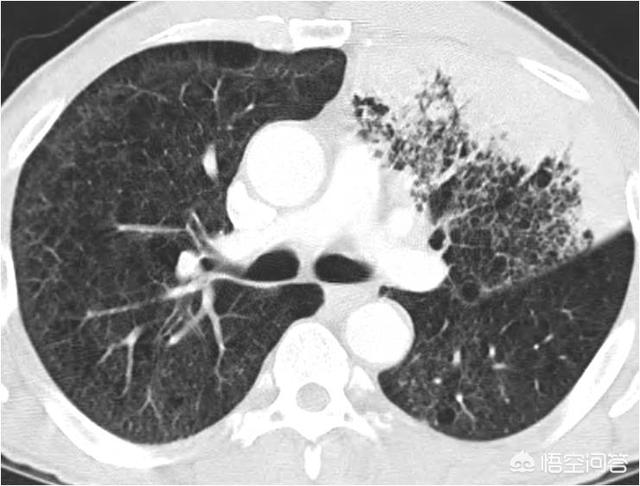

所谓肺炎型肺癌,并非一个病理学属于,而是指在影像学上表现为斑片状、大片状实变或磨玻璃样阴影,跟肺炎非常相似,但其病理基础却是肺癌的一个约定成俗,已经逐渐被淘汰的概念。

(肺炎)

通过上面两幅图,可以看出来,这种表现为斑片状影的肺癌,跟肺炎在CT上非常相似。